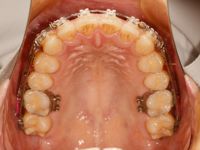

さて、ここからは今回の矯正治療の様子をご紹介します![]()

まずは調整前のお口の中です![]()

上の歯と下の歯の真ん中(正中)が一致しました![]()

![]()

下の写真は、前回の状態と今回の状態を比較したものです![]()

この1か月で上下の歯の真ん中が変化したのがわかります![]()

前回までは、上の歯の真ん中が下の真ん中より左にずれていました![]()

上下の真ん中が合っていると見栄えが良いですね![]()

下の前歯の隙間はもう閉じています![]()